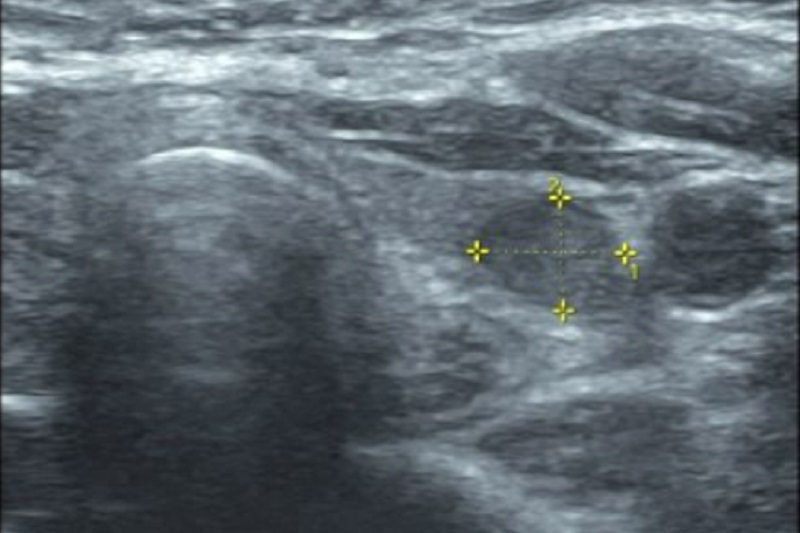

Siêu âm tuyến giáp: trên siêu âm có thể xác định kích thước, thể tích ước tính của tuyến giáp, từ đó khẳng định bệnh nhân có bướu giáp lan tỏa không. Đồng thời trên siêu âm cũng xác định được nhu mô tuyến giáp hồi âm có đồng đều không, có tăng sinh mạch không cũng như bệnh nhân có các bướu nhân không, kích thước, số lượng, vị trí của các bướu nhân tuyến giáp như thế nào.

Hình ảnh bướu nhân tuyến giáp trên siêu âm